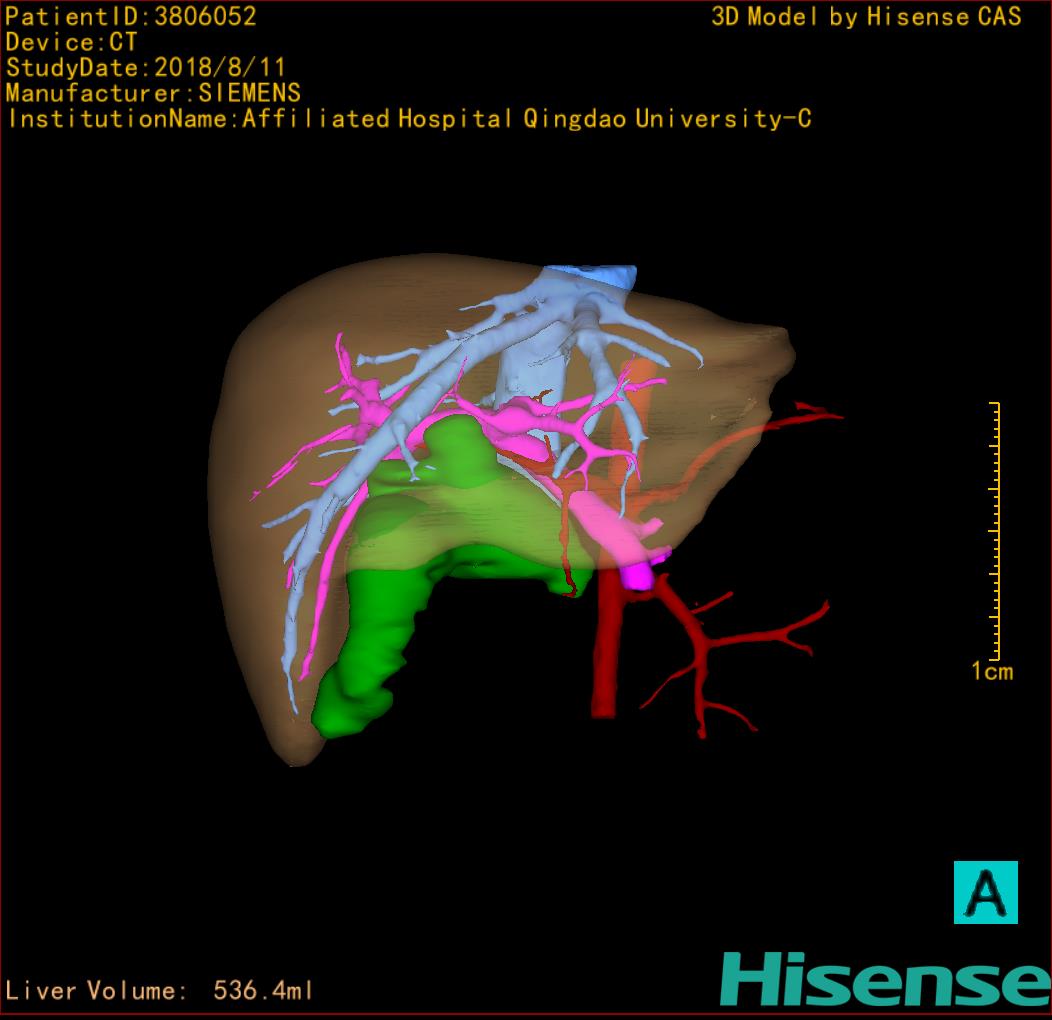

10、三维重建虚拟肝脏、胆道显像技术

三维虚拟肝脏技术是在二维影像学资料如CT等图像的基础上,通过三维重组软件和工具,比如青岛大学附属医院与海信医疗集团联合自主研发的海信计算机辅助手术系统(Hisense Computer Assisted Surgery,Hisense CAS),目前已投入临床并指导实际应用,利用该类系统对二维影像学的数据资料进行三维立体分析,重组形成立体的、有空间结构的、虚拟的肝脏三维图像。这项技术较传统的二维平面成像技术,有着明显的优势,3D虚拟肝脏技术可以构造出一个虚拟的、可视化的肝脏模型。通过对这种模型的观察,可以很容易地分辨出肝脏器官的组织结构、解剖特点,直观研究肝外胆总管的形态差异,明确肝内胆管的形态、走形、是否合并扩张、狭窄及结石,胰胆管合流的形态及共同通道内是否有狭窄、扩张和结石等病变情况,预先规划处理可能合并存在的肝内胆管扩张、狭窄或其他复杂胆道畸形,清晰地显示肝内脉管系统,包括门静脉、肝动脉及肝静脉的走行、分支,并可多角度、全方位观察病变胆道与其周围重要血管尤其是伴行的门静脉之间的解剖关系,大大提高了外科医师在术前对肝脏内部各管道结构及其变异判断的精确性和可靠性,精准地对病变进行判断和评估,还可根据患者自身的病变特点,制定出合理、个体化的手术方案,最大限度地降低术中和术后并发症发生率,并术中导航实时指导手术,提高手术的精准性和成功率。

图10:先天性胆管扩张症囊肿型三维重建虚拟肝脏、胆道显像

a 图为术前二维CT扫描图像,箭头所示为肝内胆管扩张;b 图为CT经多平面重组技术(MPR)图像后处理所得的重建图像,可显示胆总管明显扩张合并肝内胆管扩张;c 图为MRCP显示胆总管呈囊柱状扩张,直径>1 0 cm,伴肝内胆管扩张;d 图示Hisense CAS三维重建清晰显示肝脏、胆道系统及其与门静脉、肝动脉、肝静脉等之间的空间解剖关系;e 图示Hisense CAS可从任意角度以不同脏器组合显示,明确胆道系统与其伴行的门静脉系统的空间解剖关系;f 图示胆道系统立体形态及与肝脏整体的空间关系,箭头处显示肝内胆管狭窄部位发生于左右肝管汇入肝总管处。术前规划需行肝内胆管扩大成形术。